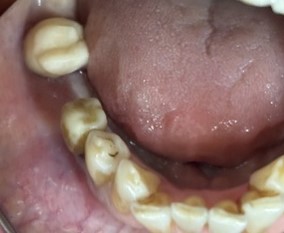

左下の抜けているところに歯を入れたい。

治療内容

インプラントを2本埋入しました。

所感

以前、1本歯がないところを、欠損の両側に被せ物をしてつないだブリッジでした。その2本のうちの前方の歯が歯根の破折を起こし、抜歯になり2本の欠損になりました。この2本の欠損を補う方法には、部分入れ歯、再度ブリッジ、インプラントの3つの方法があります。部分入れ歯もブリッジも欠損部分の負担をほかの歯に負わせるため、支台になった歯は負担が大きくなり、虫歯、歯周病、歯根破折の危険性が高まり、さらに歯を失うことになります。インプラントは、それ自身が単体で植立しているため他の歯に負担を負わすことがありませんので、咬合を回復させるだけではなく、他の歯を守る役割もあります。今回もX-Guideを使った埋入で、安心安全に行うことできました。

インプラント2本:¥363,000×2本=¥726,000(税込)

Before

After